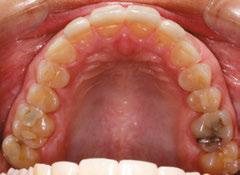

Figures 1-5: Initial dental photos

analysis showed that she had a brachycephalic skeletal pattern, but ANB and inter-incisal angles were normal. Occlusal wear in and of itself does not affect patient quality of life,3 but some patients are self-conscious about the appearance of their short, worn teeth, which is the category that this patient fits into. Her chief concern was to improve her dental esthetics.

With the anterior tooth wear, she had lost a few millimeters from the incisal edges of her teeth, which had super-erupted to maintain contact with the lower anterior teeth. The patient had a gingival height discrepancy with teeth Nos. 6-11 due to the wear and subsequent super-eruption. She had also lost tooth structure from the incisal edges on teeth Nos. 23-26 but did not want to restore the lower anterior teeth post-orthodontic treatment. Her general dentist planned on restoring teeth Nos. 7, 8, 9, and 10 with veneers or crowns.